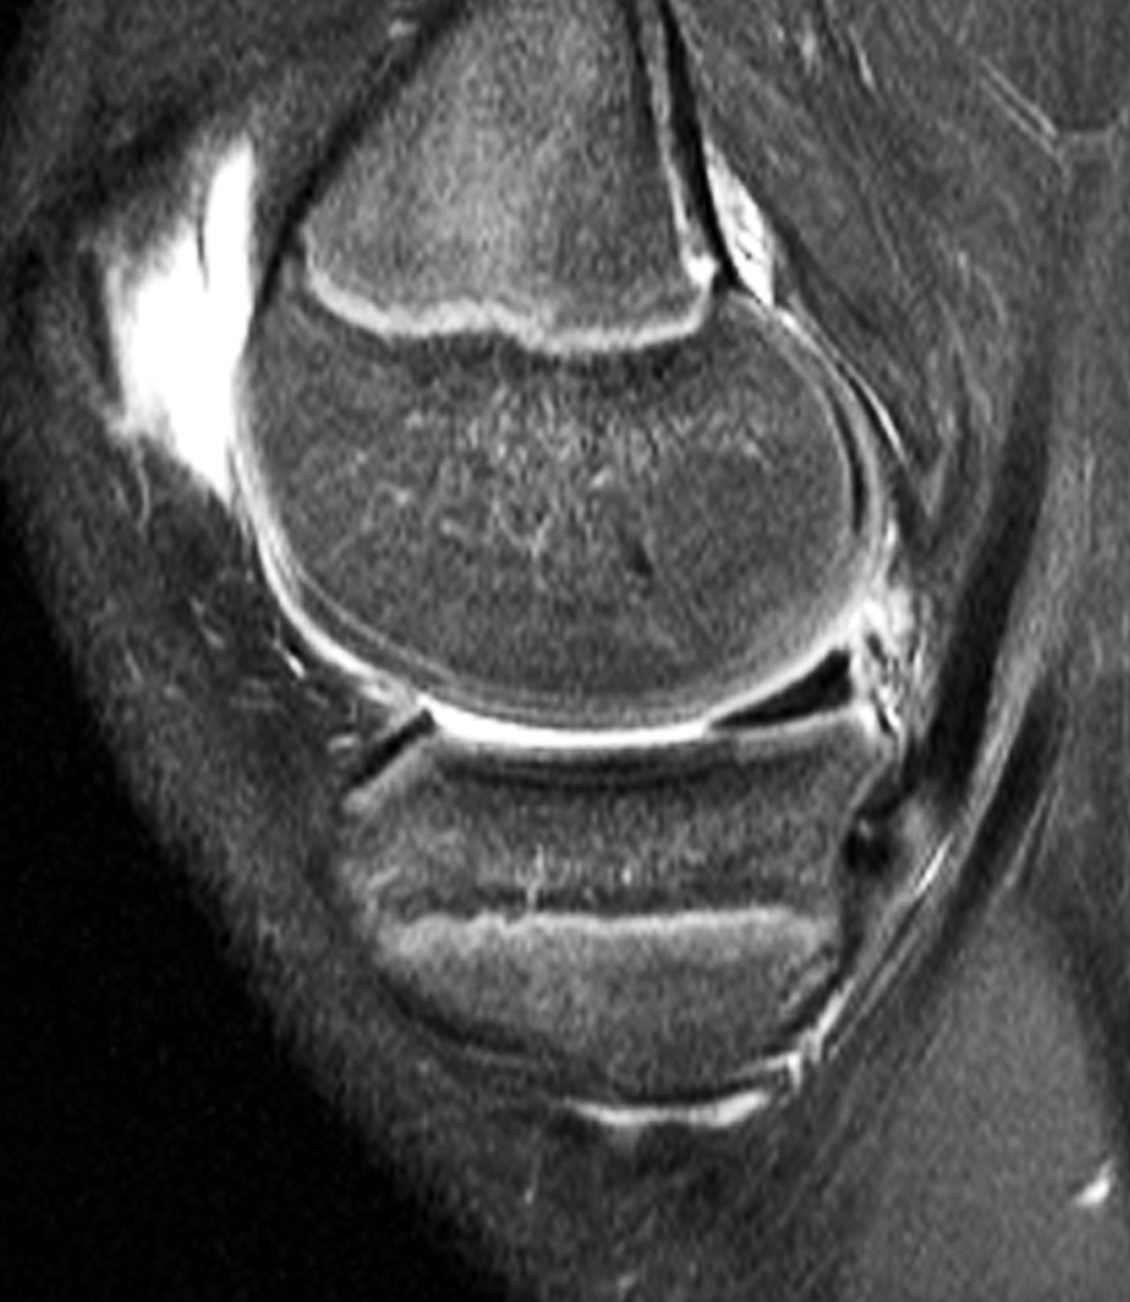

Paget Disease

In the April Radsource MRI Web Clinic, Dr. Tito Rosas discusses the MRI findings of a bone disorder commonly encountered in elderly patients. While the radiologic features are fairly easily recognizable, the MRI appearance can be variable and deceptive, especially if MRI is interpreted without the aid of other imaging studies. This Clinic details features that can help avoid misdiagnosis and aid in patient management.